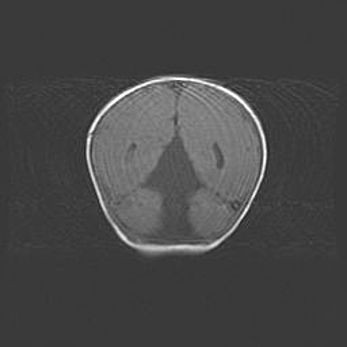

Мальформация Денди-Уокера. Киста задней черепной ямки.

Агенезия мозолистого тела.

Возраст: 2,5 месяца

Вес: 2420 г

Пол: женский

Окружность головы: 37 см

Срок гестации: 32 недели

Мальформация Денди—Уокера — редкий вид патологии ЦНС, представляющий собой врожденный порок развития каудального отдела ствола и червя мозжечка, ведущий к неполному раскрытию срединной (Мажанди) и латеральных (Лушка) апертур IV желудочка мозга. Для этогно синдрома характерна триада симптомов: гипотрофия червя мозжечка и/или полушарий мозжечка, кисты задней черепной ямки, гидроцефалия различной степени. В 70% случаев порок сочетается и с другими аномалиями головного мозга, в частности с агенезией мозолистого тела.